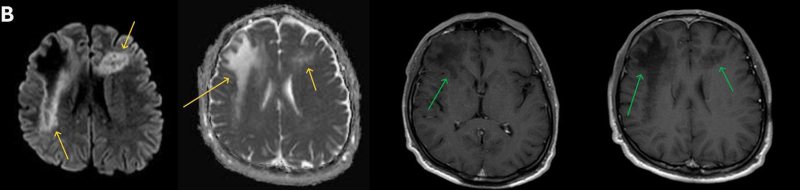

1. A) Aksiyel T2A görüntülerde bilateral sağda belirgin frontoparietal subkortikal ve derin periventriküler beyaz cevherde subkortikal U fiberleri boyunca yerleşimli sinyal artımları (oklar) izlendi.  Tarifli alanlar aksiyel T1A serilerde hipointens görünümde (oklar) izlendi.

2. B) Aksiyel diffüzyon ağırlıklı serilerde bilateral sağda belirgin frontoparietal subkortikal ve derin periventriküler beyaz cevherde periferal DAG hiperintens ADC hipointens, hafif diffüzyon kısıtlaması (oklar) eşlik etmektedir. IVKM sonrası kesitlerde tarifli alanlarda belirgin kontrast tutulumu (oklar) izlenmedi.

3. C) Tanımlanan düzeylere yönelik yapılan Perfüzyon MR incelemede belirgin perfüzyon artışı saptanmadı. Bu düzeye yönelik yapılan TE 144 multi ve single voksel MRS incelemede Cho/Cr  oranlarında hafif artış, NAA oranlarında azalma mevcuttur. Yer yer laktat pikleri görüldü.